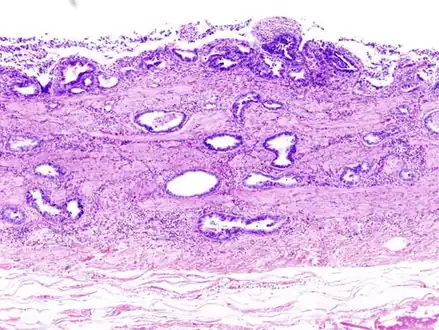

Incidentally discovered gallbladder cancer (adenocarcinoma) following a cholecystectomy.

Gallbladder adenocarcinoma histopathology